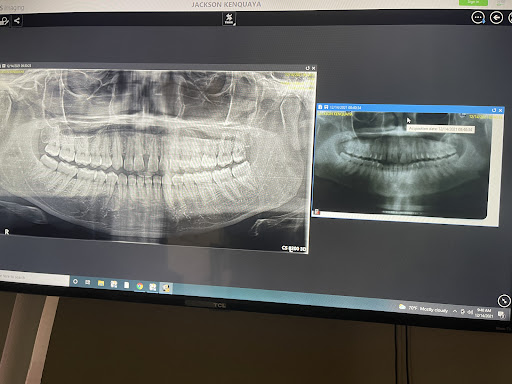

Photos

Photos of reviews